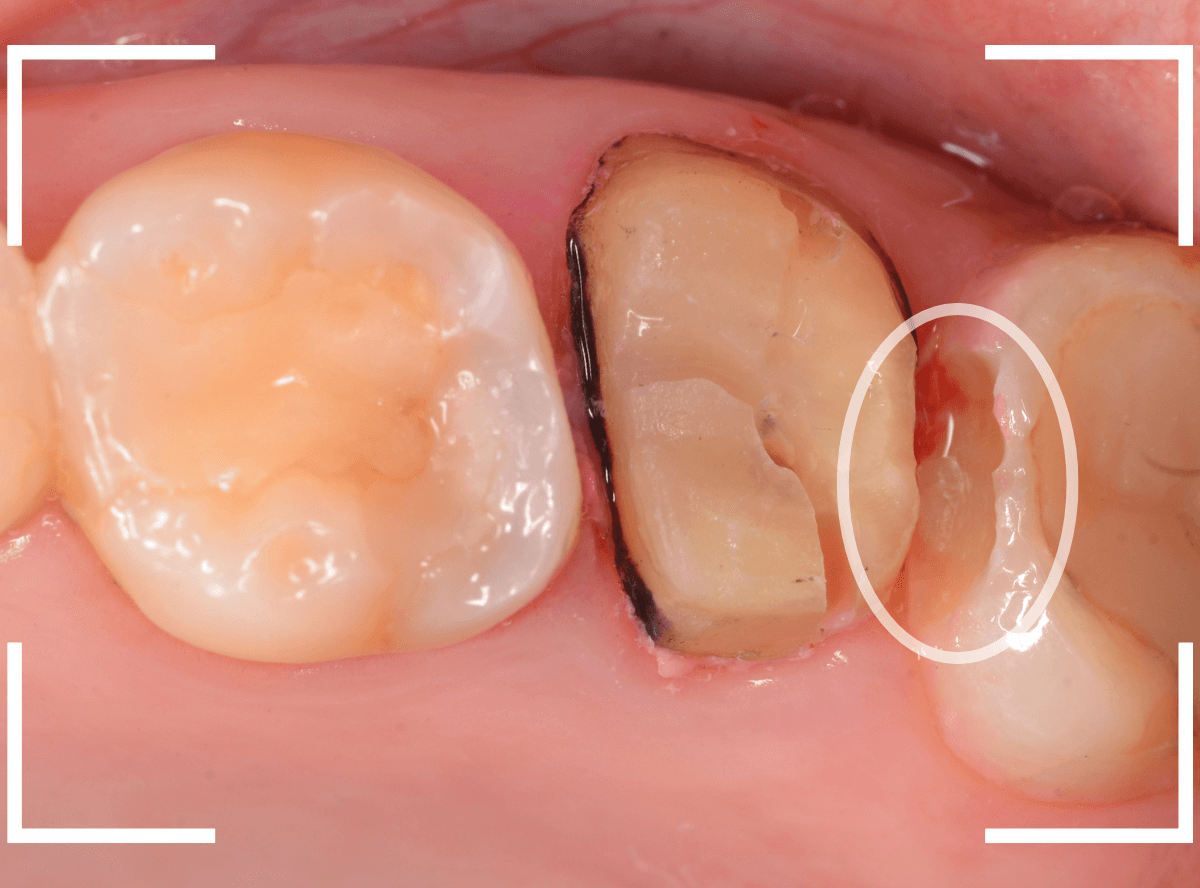

まずは、奥のメタル・クラウンを外します。

メタル・コアが入っていますが、こちらも慎重に外して、中を調べていきます。

レントゲン写真では問題なさそうでしたが、メタルコアを除去すると、中は真っ黒でした。

このように、コアの中で虫歯が進行している場合もありますので、さし歯をやり直す際は、出来る限りコアも外して調べるようにしています。

虫歯を全て除去しました。

幸い、あまり多く削る事なく進められたので良かったです。